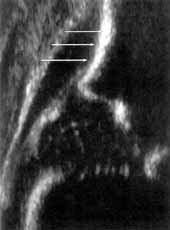

Вторая по важности координата измерений это ость подвздошной кости в средней части вертлужной впадины. На сонограмме подвздошная кость имеет четкий параллельный краю датчика контур на протяжении по меньшей мере 1 см перед суставной щелью. Однако если при установке второй координаты утерян нижний край подвздошной кости, то сонограмма, сохраняя сходство с правильной, становится абсолютно непригодной (Рис. 3).

Вторая по важности координата измерений это ость подвздошной кости в средней

части вертлужной впадины. На сонограмме подвздошная кость имеет четкий параллельный

краю датчика контур на протяжении по меньшей мере 1 см перед суставной щелью.

Однако если при установке второй координаты утерян нижний край подвздошной кости,

то сонограмма, сохраняя сходство с правильной, становится абсолютно непригодной

(Рис. 3).